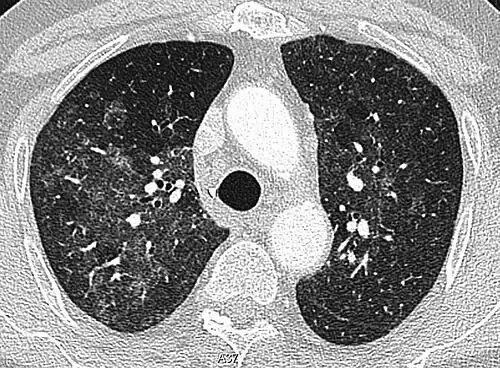

CT showing diffuse ground-glass opacities in periphery of both lungs in patient with COVID-19.

Ground-glass opacity is among the most common imaging findings in patients with confirmed COVID-19.[16][17] One systematic review found that among patients with COVID-19 and abnormal lung findings on CT, greater than 80% had GGOs, with greater than 50% having mixed GGOs and consolidation.[16] GGOs with mixed consolidation has most often been found in elderly populations.[18]

Several studies have described a pattern among initial, intermediate, and hospital discharge imaging findings in the disease course of COVID-19. Most commonly, initial CT imaging reveals bilateral GGOs at the periphery of the lungs. During initial stages, this is most often found in the lower lobes, although involvement of the upper lobes and right middle lobe has also been reported early in the disease course.[16][18] This is in contrast to the two similar coronaviruses, SARS and MERS, which more commonly involve only one lung on initial imaging.[19][20] As the COVID-19 infection progresses, GGOs typically become more diffuse and often progress to consolidation.[11][18] This is sometimes accompanied by the development of a crazy paving pattern and interlobular septal thickening.[18] In many cases the most severe pulmonary CT abnormalities occurred within 2 weeks after symptoms began.[17] At this point, many individuals begin showing resolution of consolidation and GGOs as symptoms improve. However, some patients have worsening symptoms and imaging findings, with further increase in septal thickening, GGOs, and consolidation. These patients may develop lung "white-out" with progression to acute respiratory distress syndrome (ARDS) requiring treatment escalation.[17][21]